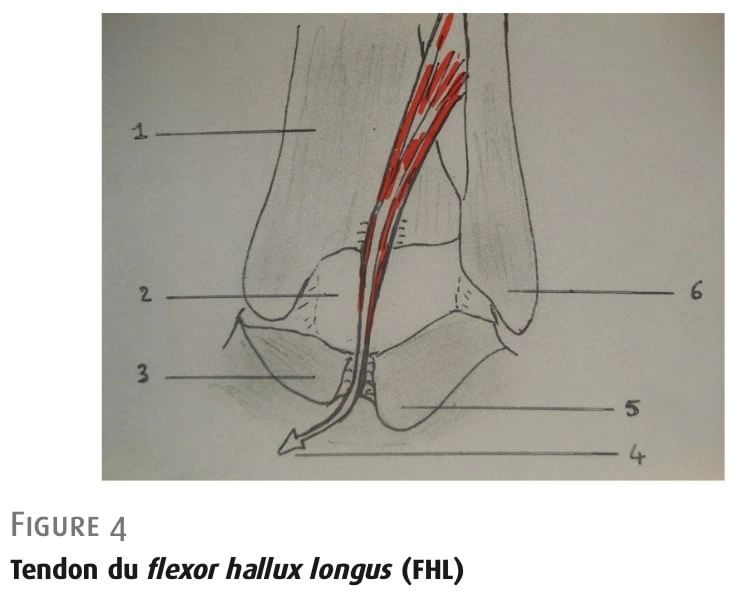

屈肌(FHL)肌腱

肌腱被滑膜鞘包围,垂直穿过胫骨沟,然后穿过趾间沟,由后环韧带封闭。 然后它改变方向,在距骨支撑下面向下和向前延伸(图 4)。 其内侧即为胫骨后神经血管束。

图 4: 屈肌肌腱。